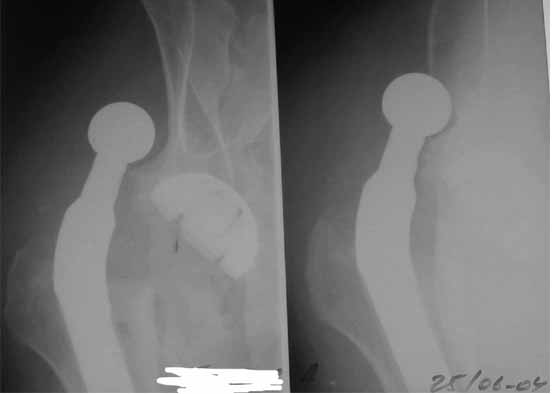

Re: вывих головки эндопротеза

Во вложении - рентгенограммы после вывиха и после вправления.